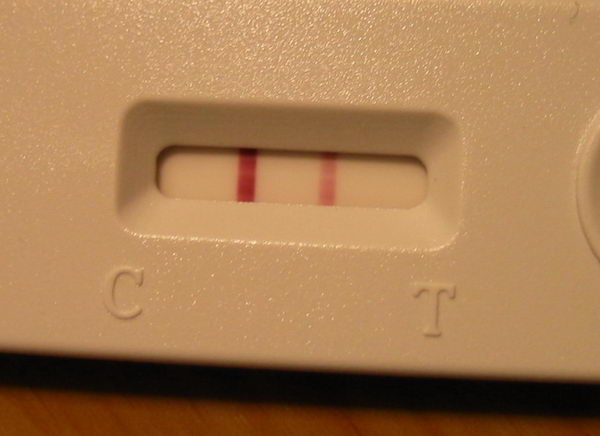

Húha!!! Ez nagyon bíztató! Drukkok!! Amúgy meg miért vársz erősebbet a 12. dpo-n?? 14. dpo előtt nem is érdemes igazán tesztelni. Úgyhogy ez tuti pozitív!!

Drukk!! De nem faldni, ha nem csíkos. 13. dpo még kicsit korai.